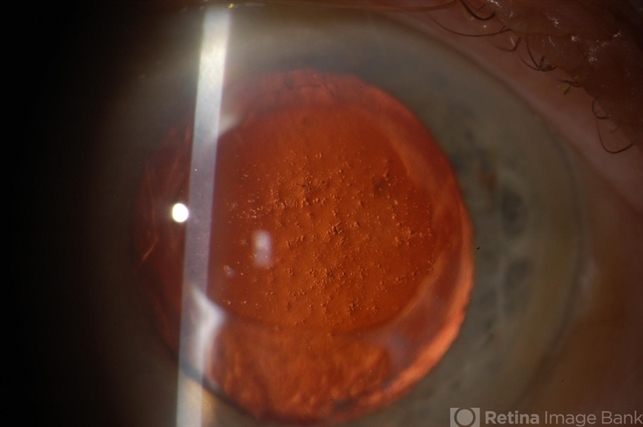

Gavin Thorsrud (November 21 2013)amyloid corneal degeneration - retro. illumination view

- corneal degeneration, amyloid

- Amyloid degeneration of the cornea.